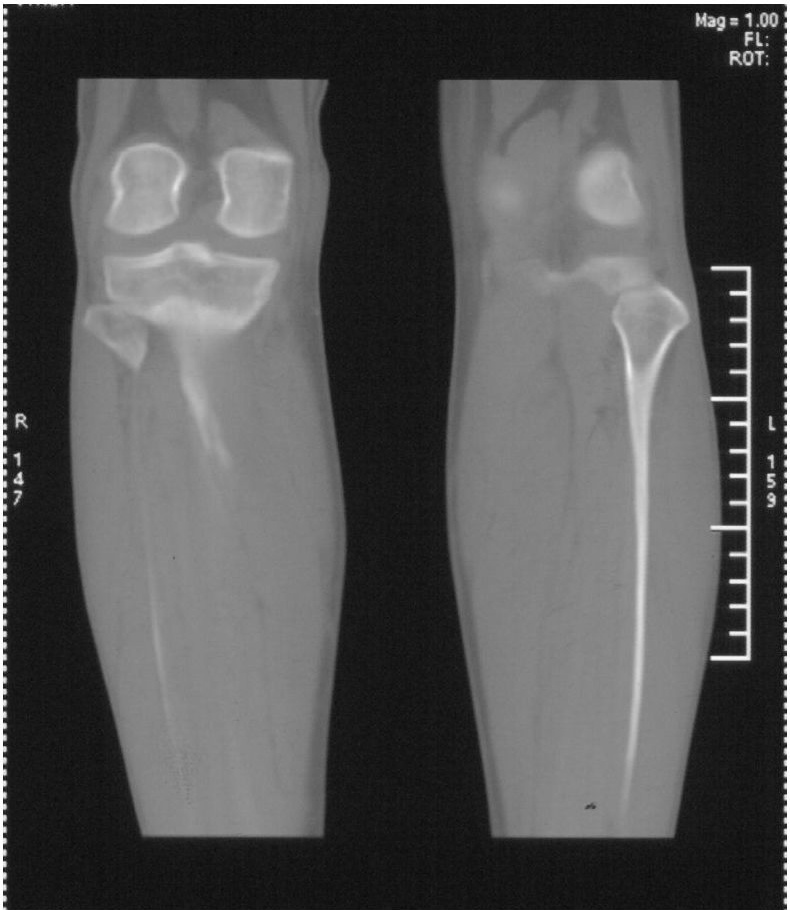

标题: 病例追踪

该患者到某三级医院进行会诊,并重新作了平片检查,认为畸形性行骨炎: